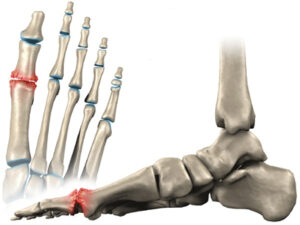

El Hallux Rigidus es una patología que impide la dorsiflexión de la articulación del Hallux (dedo gordo del pie).

Se caracteriza por una artrosis osteofítica, degenerativa y anquilosante de la primera articulación metatarsofalángica. El Hallux Rigidus es uno de los problemas más frecuentes del primer dedo del pie.

En estadios avanzados, a la hora de caminar no se puede ejecutar el paso correctamente, limitando así la fase en la que el pie despega del suelo (3º rocker o balancín del pie).

Esta articulación es fundamental a la hora de levantar el talón al realizar el paso, así como para saltar o correr. Además, nos ayuda a mantener el equilibrio cuando estamos de pie. Por esta razón, el diagnóstico precoz y un tratamiento adecuado son decisivos para corregir y evitar la evolución del Hallux Rigidus.